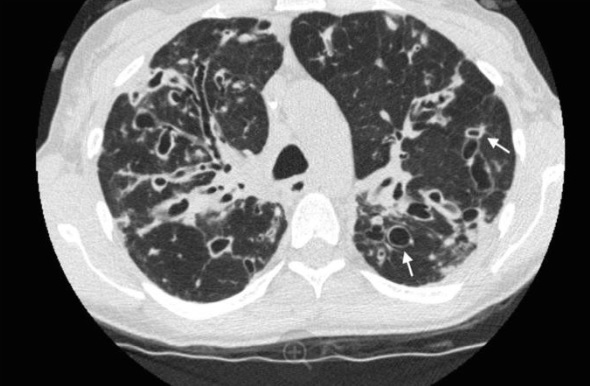

¿Cuál es el diagnóstico?

A

Bronquiectasias